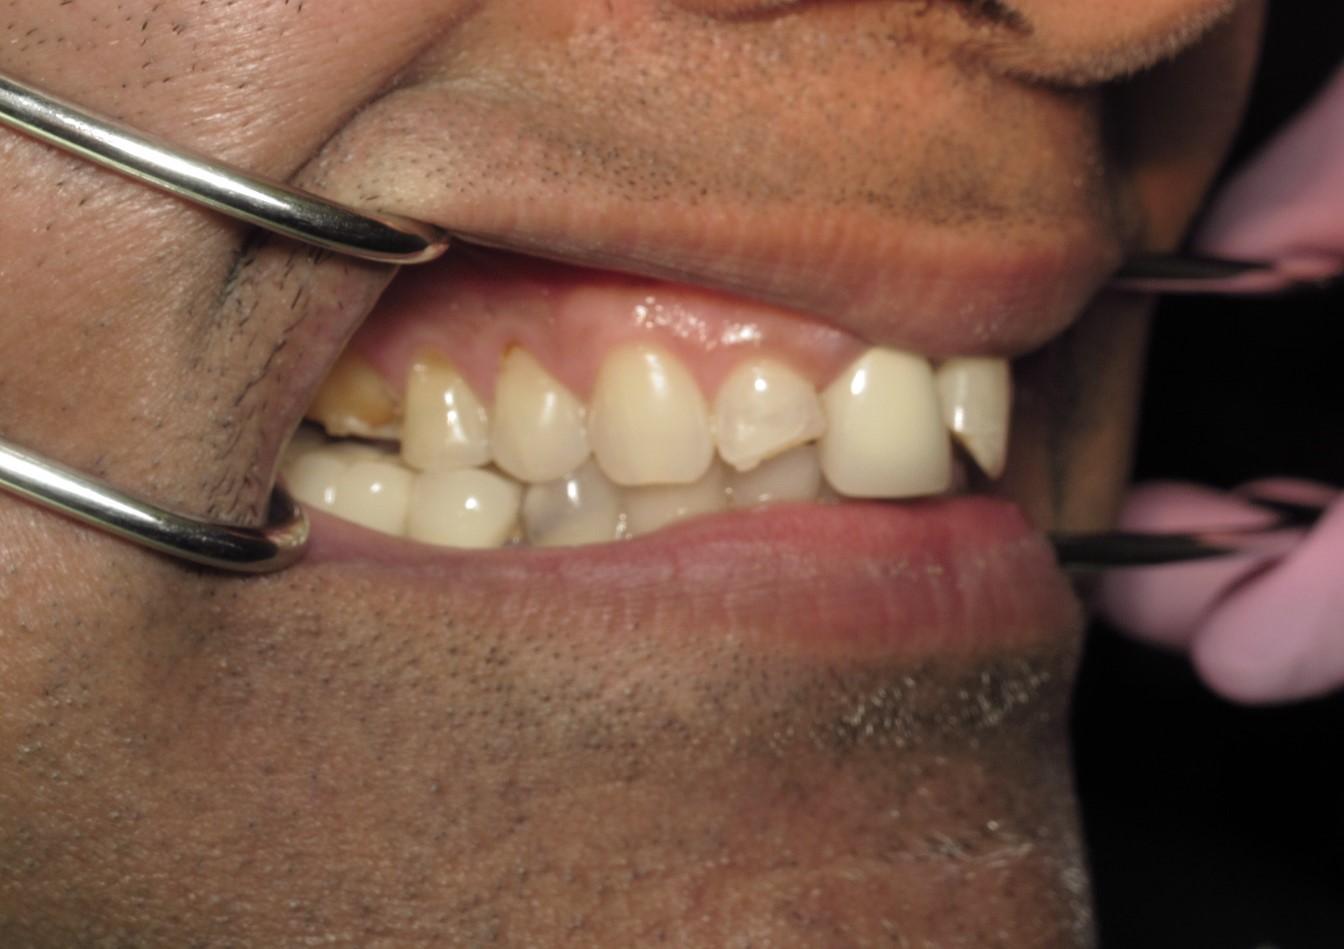

https://demo.discussdentistry.com/forums/topic/accident-victim-upper-arch-rehab/#post-26049 <![CDATA[Accident victim => Upper arch rehab]]> https://demo.discussdentistry.com/forums/topic/accident-victim-upper-arch-rehab/#post-26049 Tue, 30 Apr 2024 04:28:51 +0000 Amit Kumar The patient presents after falling in the bathroom and hitting his face on the countertop.  Previously, he had a PFM crown in the upper anterior.  He needed root canal therapy.

The patient is a stage performer (actor) and has appeared in some minor film roles, so he wanted to restore his teeth so that his smile would appear “white” on camera.

The patient’s lower teeth need attention and we will start the process once the patient’s finances have improved.

eMax material was used.  Pics were taken immediately after cementation.Before LeftBefore FrontBefore RightAfter FrontAfter LeftAfter Right